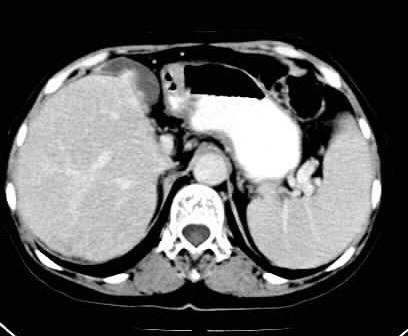

标题: CT24035:肝内占位

右叶后段血管瘤,层面少,看不见左叶,脾大。

血管瘤、肝左叶缺如、脾稍大。

肝右叶后段低密度块影,增强后造影剂逐渐向病灶充填,支持肝血管瘤。